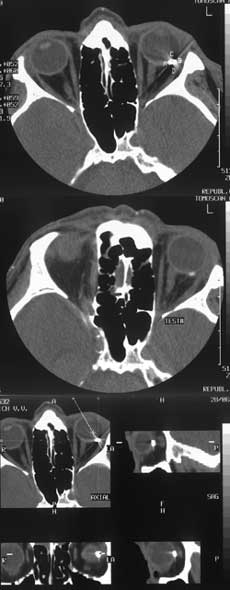

Применение компьютерной томографии в диагностике ранений заднего полюса глазного яблока.

Рис. 2. Применение мультипланарных реконструкций позволяет определить точную локализацию инородного тела по отношению к структурам орбиты, его взаимоотношение с оболочками глазного яблока.